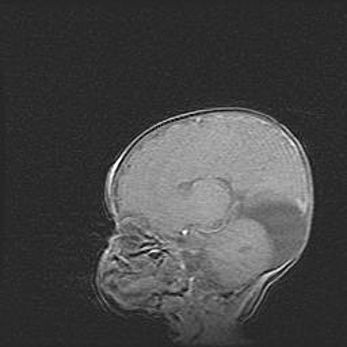

Аномалия Денди-Уокера. Признаки гипоплазии мозолистого тела.

Возраст: 5 месяцев 3 дня

Вес: 5550 г

Пол: мужской

Окружность головы: 39 см

Срок гестации: 40 недель

Аномалия Денди-Уокера – это порок развития головного мозга, для которого характерна триада симптомов: гипотрофия или аплазия червя мозжечка и/или полушарий мозжечка, расширение четвёртого желудочка с формированием ликворной кисты задней черепной ямки, гипертензионная гидроцефалия различной степени.

Гипоплазия мозолистого тела относится к дефектам внутриутробного этапа развития мозговой ткани, возникающим в процессе закладки структур головного мозга, что происходит на начальных этапах развития эмбриона.